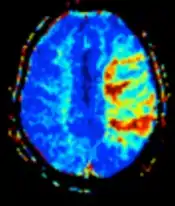

Perfusion weighted (PWI) Dynamic susceptibility contrastDSCMeasures changes over time in susceptibility-induced signal loss due to gadolinium contrast injection.[32]

• Provides measurements of blood flow

• In cerebral infarction, the infarcted core and the penumbra have decreased perfusion and delayed contrast arrival (pictured).[33]